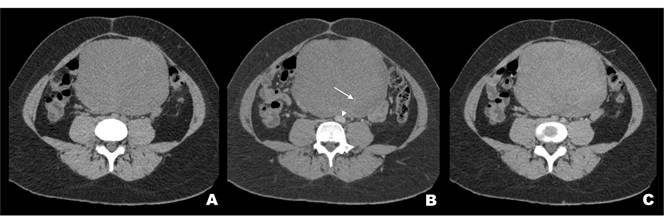

Al examen físico se encontró una masa abdominal de gran volumen en la región periumbilical, bien delimitada, no adherida a planos profundos, de consistencia blanda, superficie lisa y levemente dolorosa. Se planteó el diagnóstico de abdomen agudo quirúrgico y se solicitó una tomografía computarizada (TC) de abdomen y pelvis que confirmó la presencia de una masa intraperitoneal central bien delimitada, levemente hipodensa, homogénea, en contacto con la pared abdominal y que causaba desplazamiento de las asas intestinales. Con el uso de medio de contraste intravenoso se observó un leve realce homogéneo que persistía en la fase tardía (Figura 1).

En la actualidad, los pacientes con dolor o masas abdominales suelen ser sometidos a estudio mediante imágenes diagnósticas que, por su alta sensibilidad y especificidad y su fácil disponibilidad, permiten orientar hacia el tratamiento quirúrgico, por lo que la imagenología cumple un rol fundamental para determinar la extensión, efecto de masa y evaluar el potencial de resecabilidad. En la tomografía computarizada se visualizan como tumores bien definidos, relativamente isodensos al músculo y que presentan leve realce con el uso de contraste intravenoso, en caso de degeneración o necrosis se puede observar una densidad heterogénea. Dependiendo del grado de infiltración adyacente puede existir dificultad en distinguir los márgenes 10. La resonancia magnética (RM) es el examen de elección por la evaluación óptima que hace del tejido blando y su relación con estructuras adyacentes. Una mayor intensidad de señal en secuencias potenciadas en T2 se relaciona directamente con la velocidad de crecimiento celular 11.